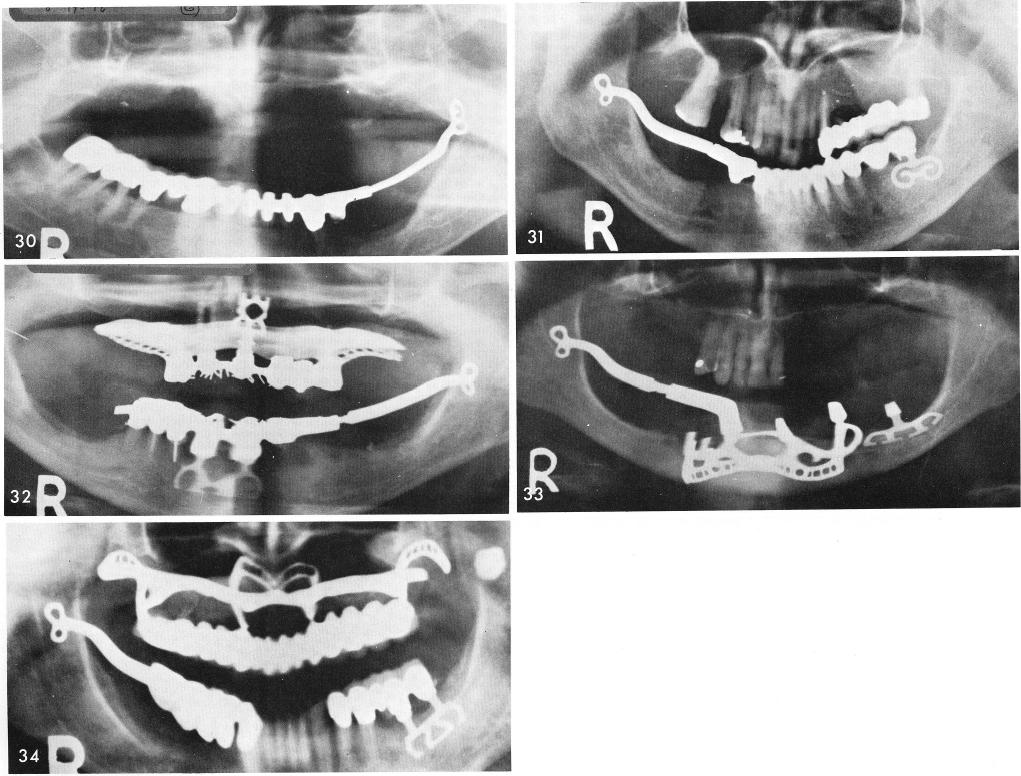

is excellent, fig. 27. The unilateral fixed left posterior restoration is completed and cemented over the cable, figs. 28, 29. The finished x-ray, fig. 30. Figs. 31, 32, 33, 34 shows x-rays of other unilateral sliding cables cases.

1 X-rays of unilateral mandibular sliding cables for ramus implants